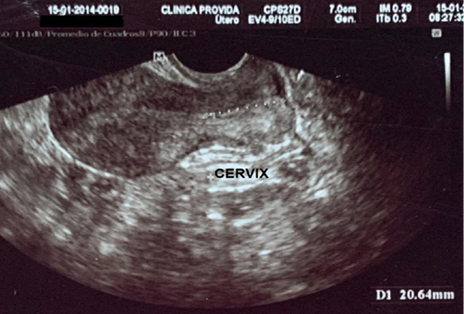

Antecedentes patológicos personales: incompetencia cervical, más aborto recurrente. Se observa la longitud cervical y longitud de útero previo al primer cerclaje en la Figura 1 y 2. Antecedentes quirúrgicos: cerclaje cervical por vía vaginal en la tercera gesta. Antecedentes gineco-obstétricos: menarquia 12 años, ciclos menstruales regulares, duración de 6 días, sangrado moderado. Gestas 4, partos 0, abortos 3, cesáreas 0, hijos vivos 0.

Figura 1. Longitud cérvix uterino por ecografía transvaginal .

Fuente: Servicio de Ginecología-Obstetricia, Hospital Básico “PROVIDA”